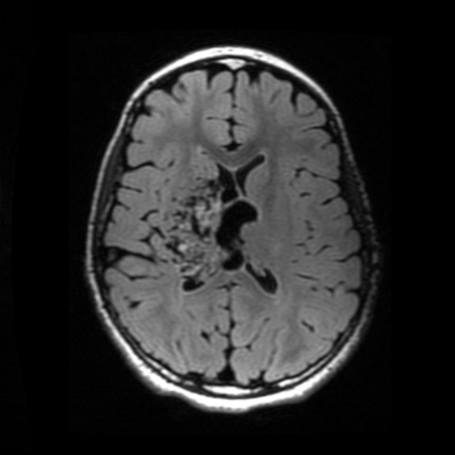

Malformaciones Arteriovenosas

Tipos: Las malformaciones arteriovenosas (MAV) son conexiones anormales entre arterias y venas sin capilares intermedios. Pueden ser cerebrales o medulares y variar en tamaño y localización, con riesgo de sangrado.

Diagnóstico: Se realiza mediante tomografía computarizada (TAC) en casos de hemorragia, resonancia magnética (RM) para evaluación estructural , angiotomografía cerebral que es uno de los estudios más específicos. Y en algunos casos seleccionados angiografía